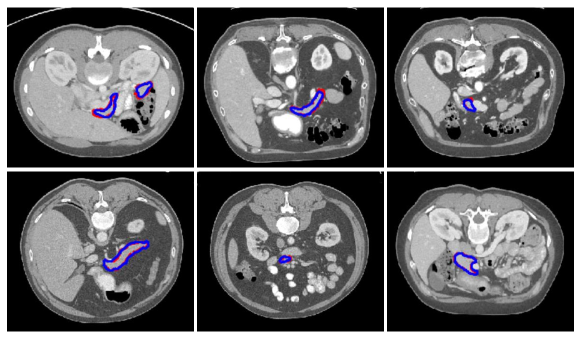

Refer to caption

Figure 5: Sample segmentation results of the pancreas CT images. The red and blue contours are the ground truth and our segmentation results, respectively.

4.3 Pancreas Segmentation

To evaluate the proposed architecture, we compare the performance of the model against other state-of-the-art CT pancreas segmentation methods. The results are summarized in Table 3. It can be seen that our proposed model achieved 83.9 ±plus-or-minus\pm 4.51 in DSC for pancreas labels, which outperform other state-of-the-art methods. Several example segmentation results of our proposed method are shown in Fig. 5. Our proposed model can accurately segment the pancreas from CT images. It is worth noting that we only employ a single model to segment pancreas and our model does not require multiple CNN models as in roth2018spatial .